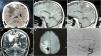

We present a case of an adult patient who received radiosurgery for treatment of an unruptured parietal arteriovenous malformation. He was followed-up for 10 years and angiographic cure was documented. Fifteen-years after radiosurgery, he complained of new-onset progressive focal seizures associated with a thrombosed venous aneurysm with persistent arteriovenous shunt angiographically occult but evidenced intraoperatively. After resection of the lesion, symptoms disappeared.

This case depicts a symptomatic thrombosed venous aneurysm presenting as a rare delayed complication of radiosurgery for the treatment of brain arteriovenous malformation, which can be associated with angiographically-occult persistent arteriovenous shunt.